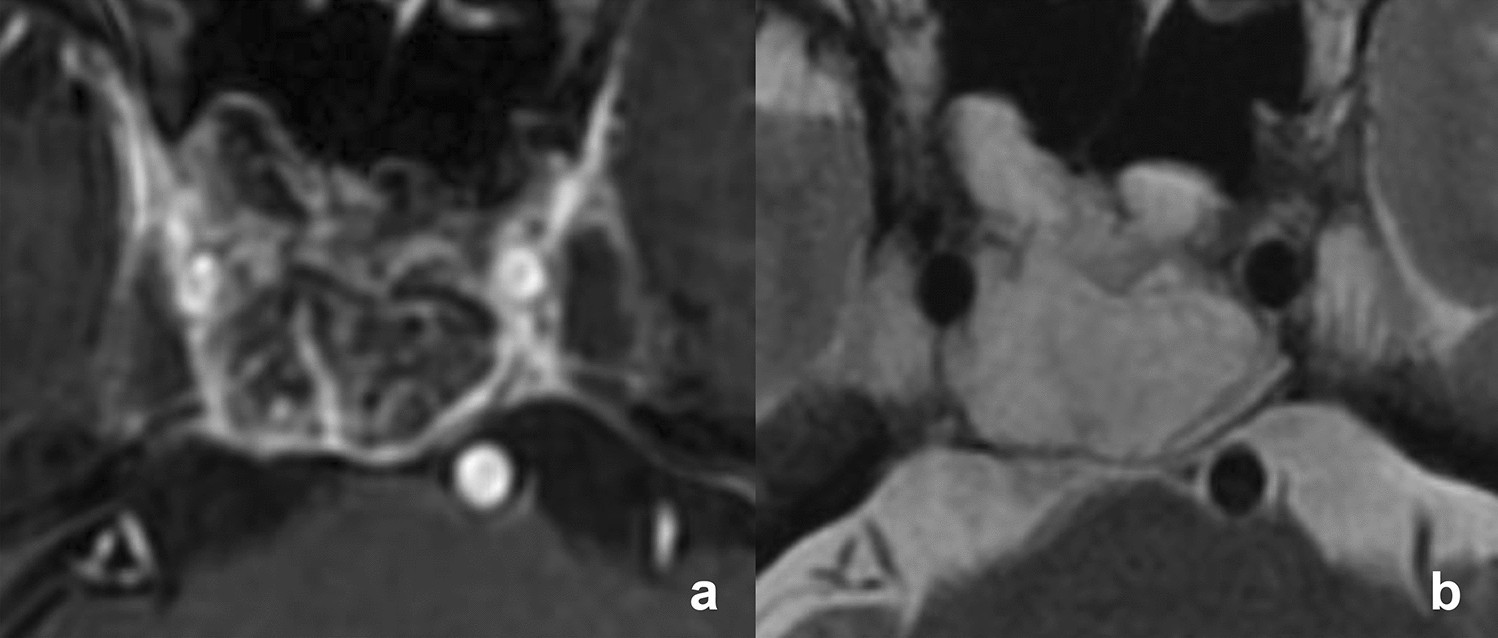

Magnetic resonance imaging of stroma-poor chordoma. (a) Contrast-enhanced T1-weighted and (b) T2-weighted imaging show a poorly enhancing mass originating from the clivus with T2 high signal intensity.